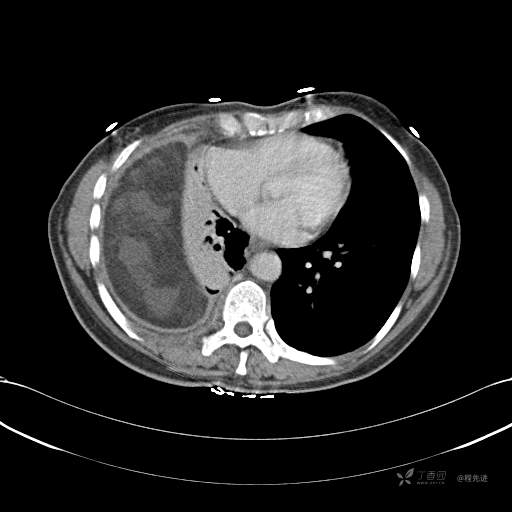

患者性别:女

患者年龄:51岁

简要病史:胸闷半年